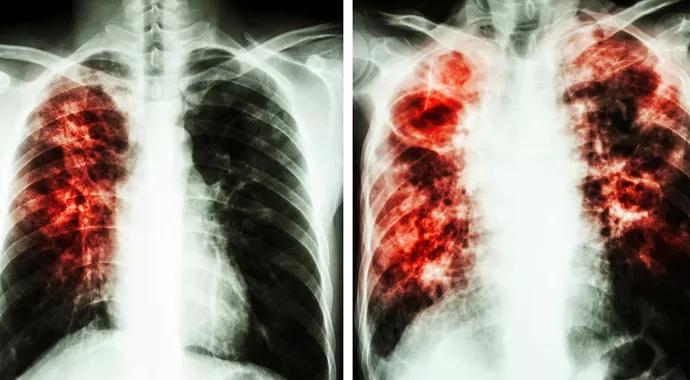

Promising Emerging Therapies for the Treatment of Idiopathic Pulmonary Fibrosis

Clinical trials necessary to cure devastating disorder

The FDA approval of pirfenidone and nintedanib in October 2014 as the first-ever treatments for idiopathic pulmonary fibrosis (IPF) represented the culmination of decades of research into the mechanisms underlying this devastating disorder.

The understanding of this disease as an epithelial-cell-driven aberrant wound healing process orchestrated by transforming growth factor beta (TGF-β) not only led researchers to study these two agents, but opened the door for a number of other therapies. Many of the agents under investigation have the exciting potential to not only slow fibrosis, but halt and even reverse the fibroproliferative cycle in IPF.

A number of lines of evidence suggest that no single agent is responsible for the lung injury seen in IPF, but that individuals with IPF have intrinsic epithelial cell defects that render the epithelial cell susceptible to repetitive injury from any number of environmental agents (e.g. cigarette smoke, acid reflux, viral infections). This injury leads to aberrant signaling between the lung epithelium and mesenchyme, resulting in a persistent, abnormal wound healing response.